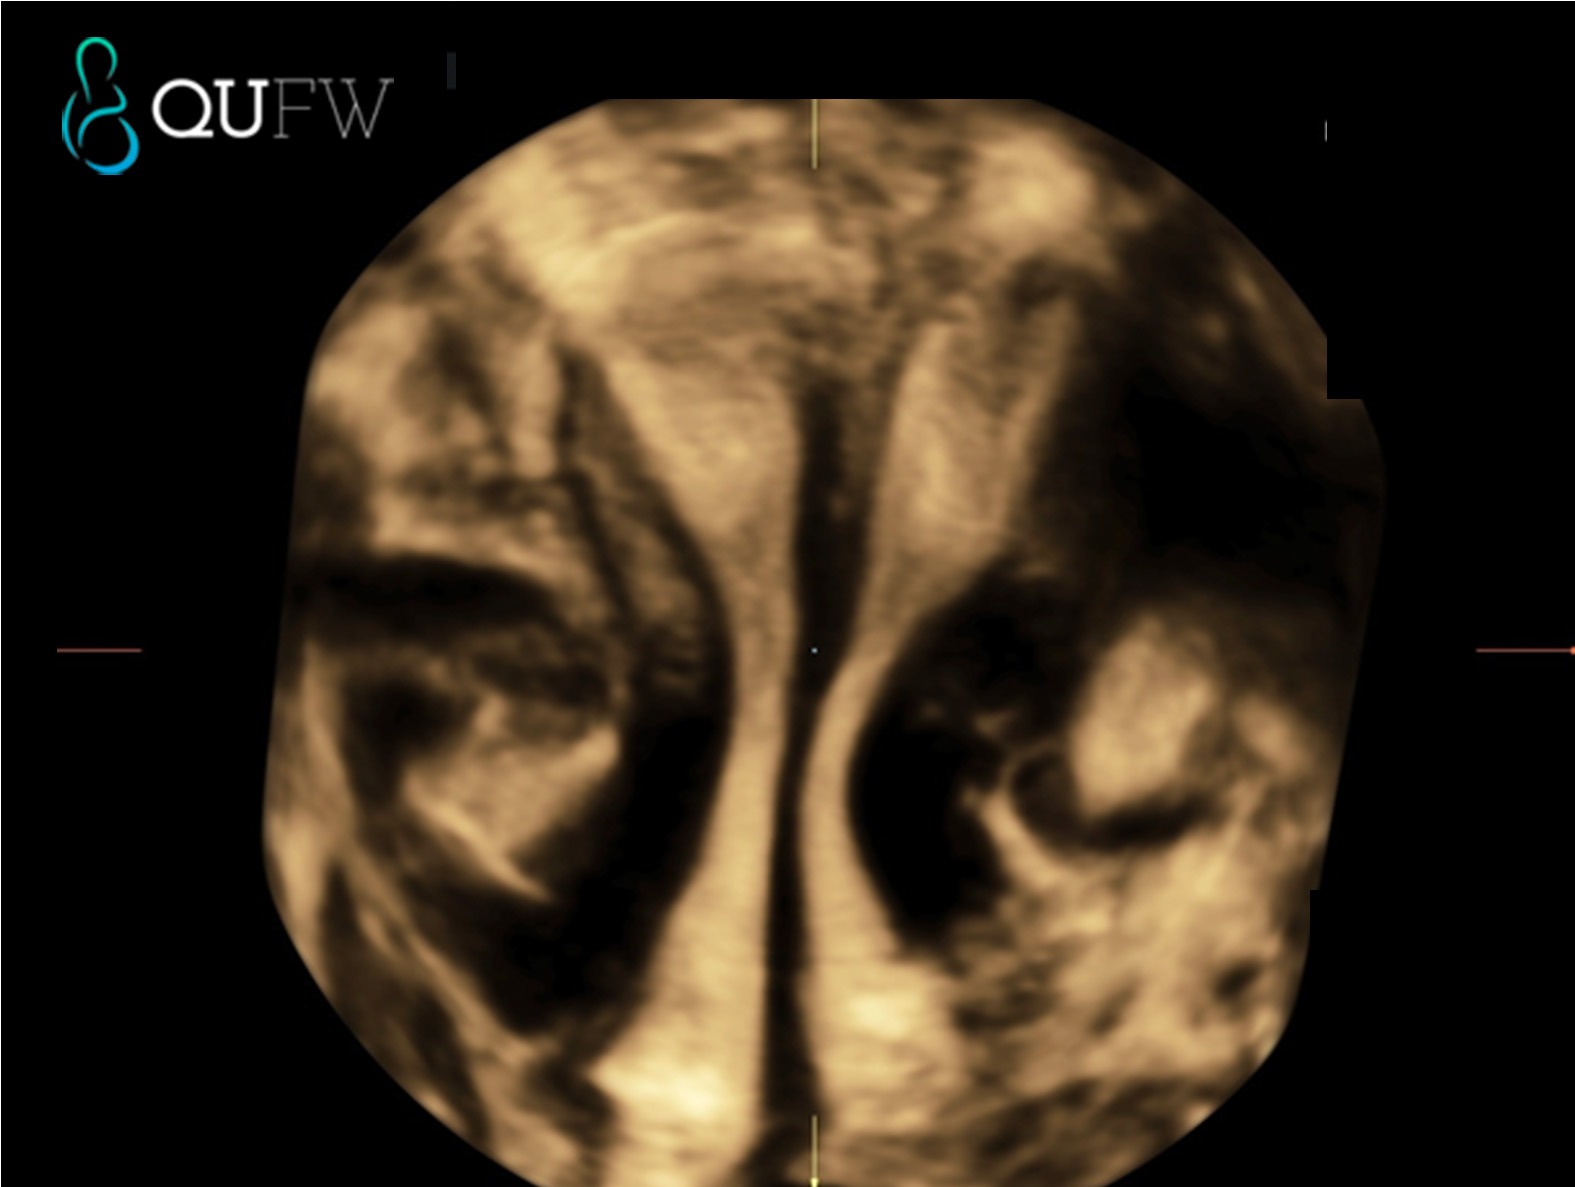

3D reconstructed coronal image of the uterus